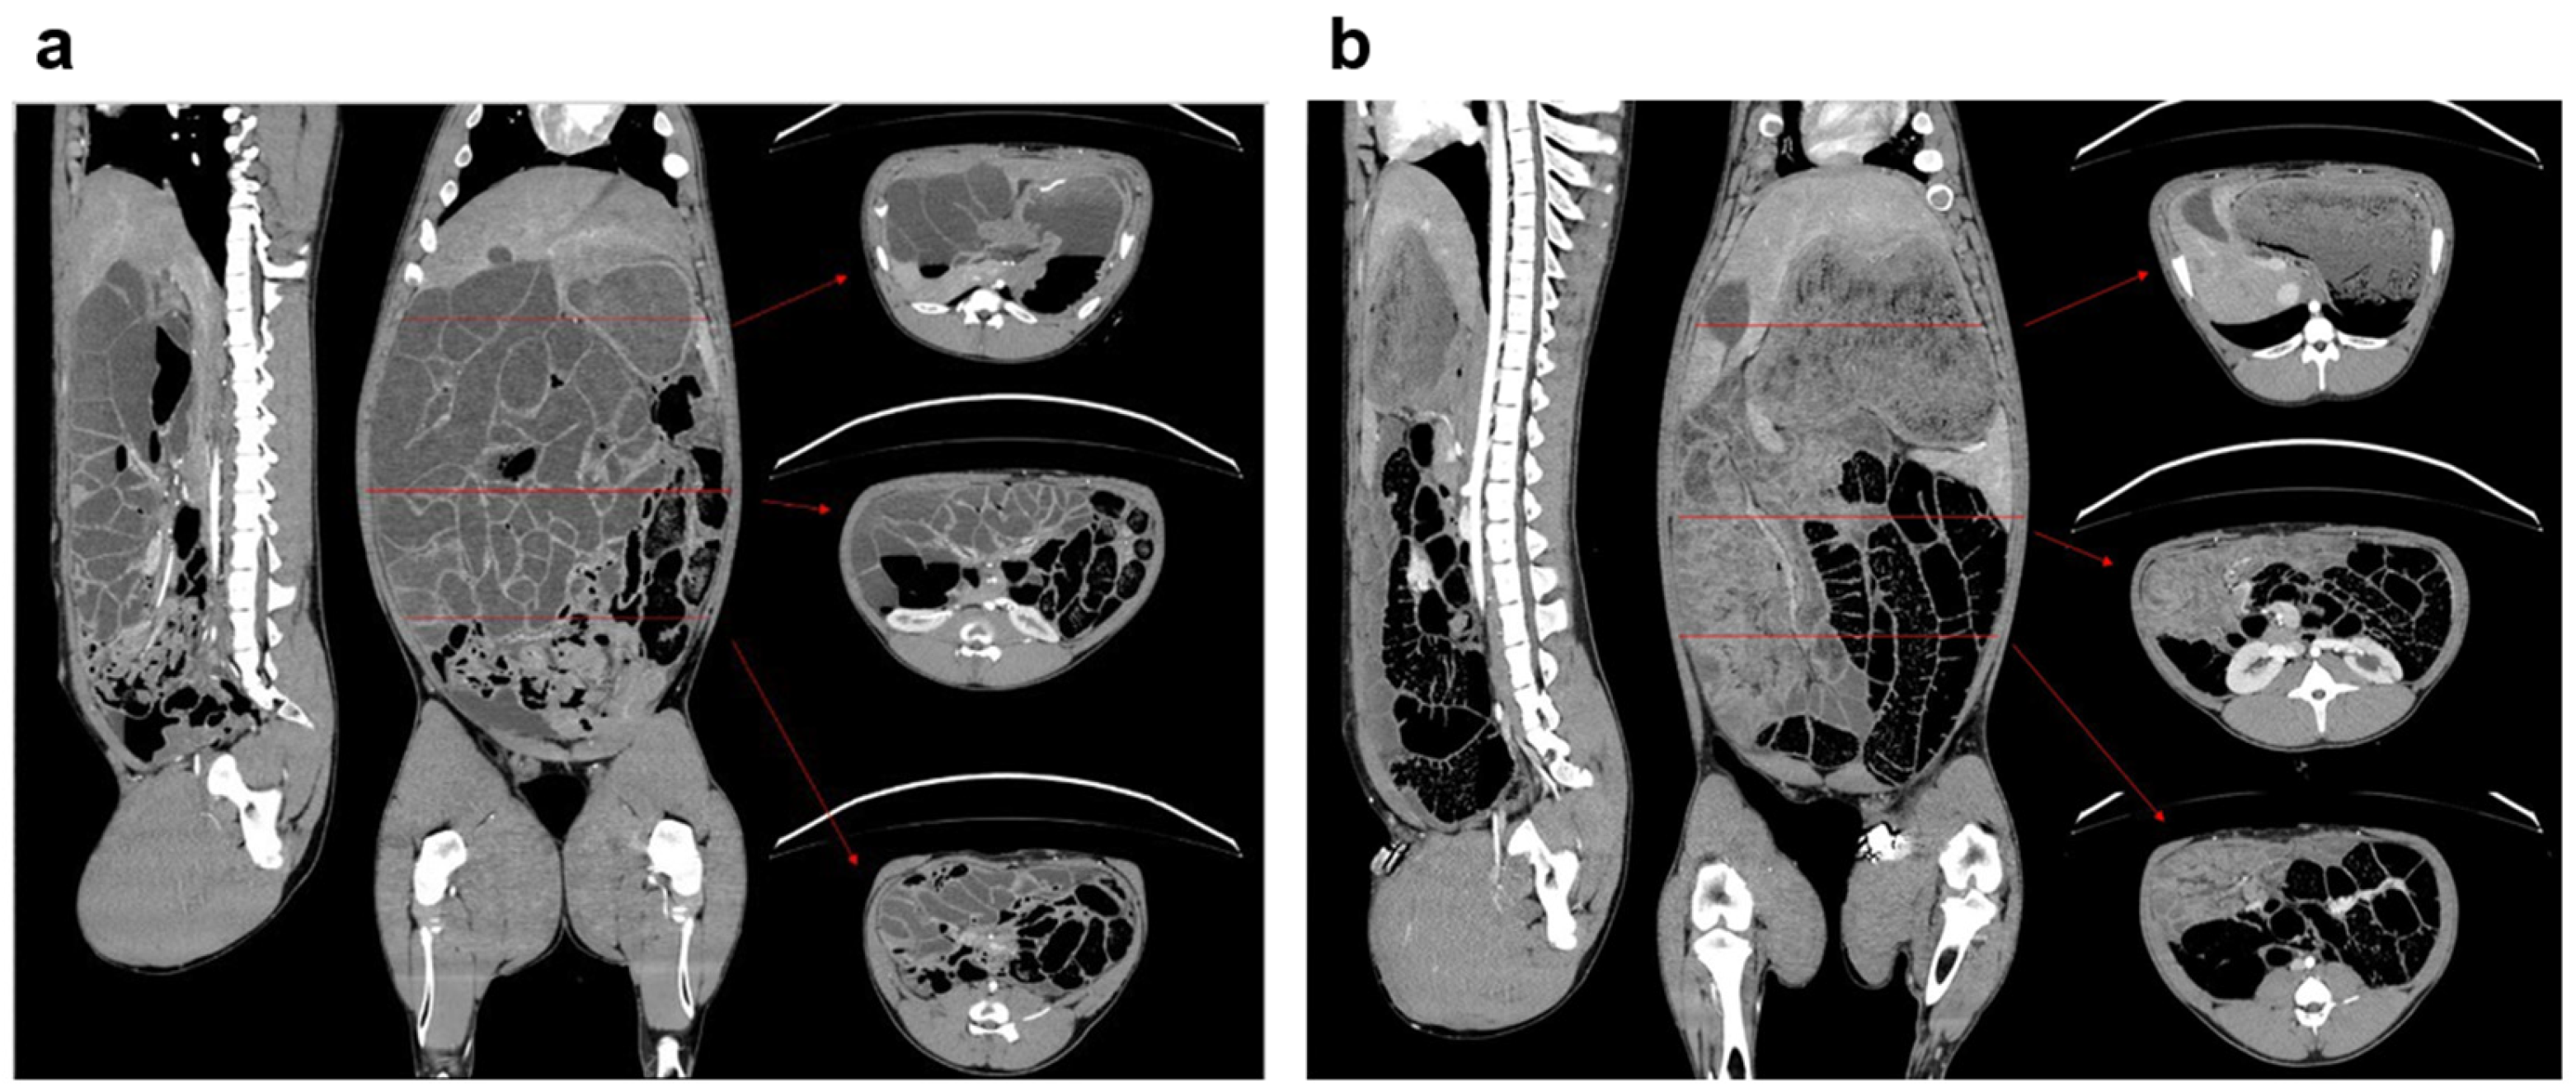

3.1. General Model Characteristics and Pathology